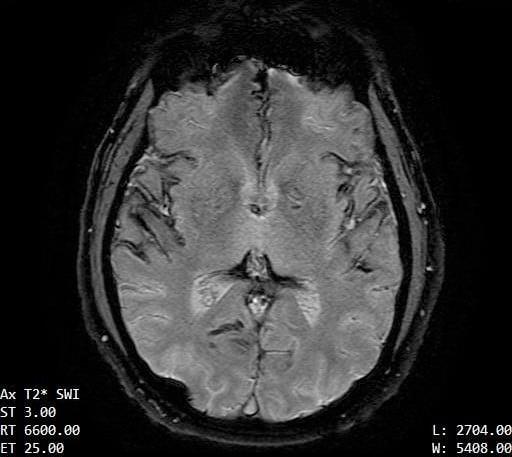

The contours of the cerebrum, cerebellum, and brainstem are outlined with a T2 hypointense signal with blooming on susceptibility weighted sequences, which is compatible with the clinical history of superficial siderosis. A majority of the T2 hypointense signal is present in the superior folia of the cerebellum but also seen coating the surfaces of the brainstem, the cortical surfaces along the Sylvian fissures, and the cortical surfaces of the paramedian sulci of the frontal and occipital lobes. Few subcortical and periventricular T2/FLAIR hyperintensities are present in both cerebral hemispheres.²

If you look at each image, you can see the dark areas where his hemosiderin deposits are. The radiologist will use the same machine and settings, so we should visually compare the new images with these for some positive change.³